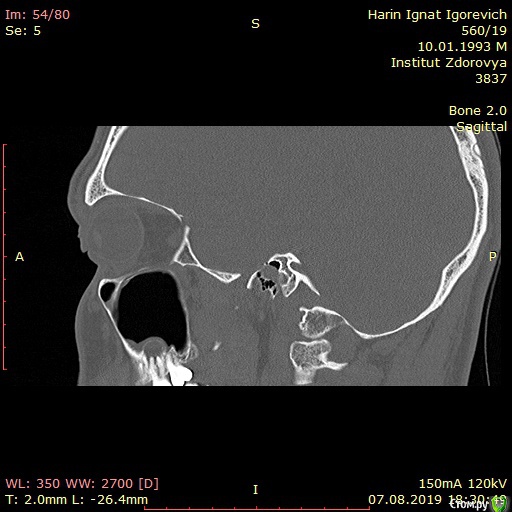

Игнат46 Опубликовано 9 декабря, 2019 Поделиться Опубликовано 9 декабря, 2019 Ищу клинику и специалиста для лечения кист.Сделал КТ пазух носа, и обнаружились кисты на корнях двух зубов. Ничего не беспокоило, прошел месяц, а сейчас уже второй день чувствую боль при нажатии на десну в этой области и некоторую опухлость . Ссылка на комментарий